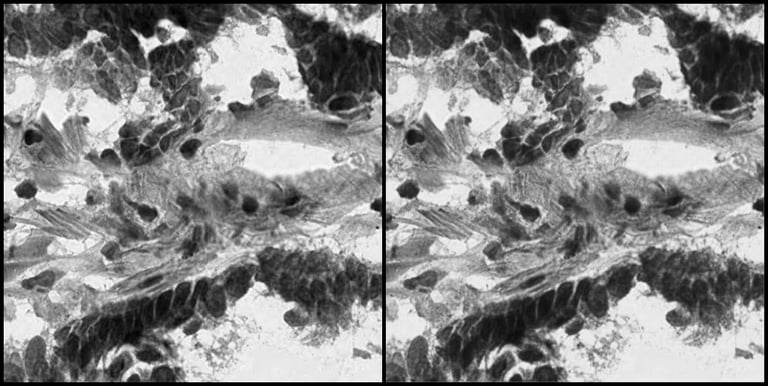

Side-by-side comparison of the Original Histopathology Image and the Reconstructed Image by the Autoencoder Model.

To understand how effectively the autoencoder captures the biological reality of a tumor cell, we can look at the model's inputs and outputs. On the left side of the image is the original histopathology slide tile, containing highly complex cellular morphologies. On the right is the image reconstructed by the AI after the data has been compressed into the most important data features. The best-performing autoencoder model in this study achieved a Mean Squared Error (MSE) reconstruction error of just 0.43%. This low error rate, along with the visual reconstruction demonstrate that the mathematical "fingerprints" the AI extracts are not losing critical biological information—they retain the exact structural features needed for accurate downstream analysis.